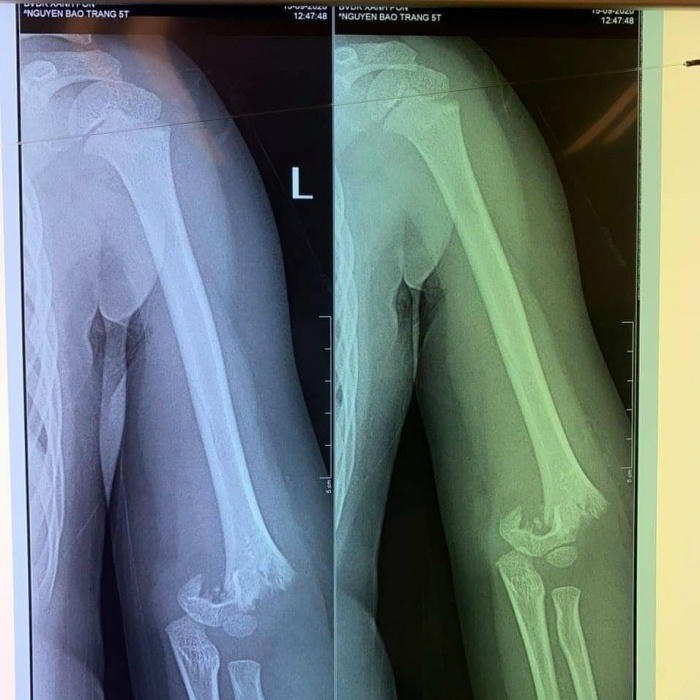

Khi cô giáo ra thông báo mẹ vào để làm thủ tục nhập viện mổ cho con, chị H vô cùng đau xót khi bác sĩ chẩn đoán tình trạng cháu P phải mổ cấp cứu ngay lập tức vì bị gãy phần trên xương cánh tay.